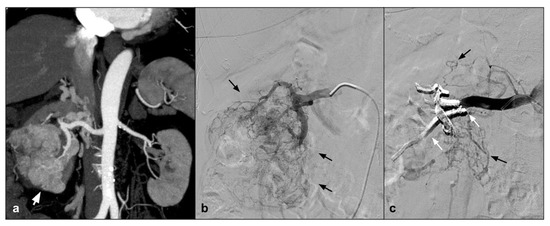

7. Endoleak

Endovascular abdominal and thoracic aortic aneurysm repair (EVAR and TEVAR) in patients with a suitable anatomy has become the preferred treatment for abdominal aortic aneurysm [44]. Those endovascular procedures provide a less invasive alternative to open repair with improved outcomes. The most common complication is represented by endoleaks, which may compromise long-term endograft viability, increasing the risk of rupture; therefore, long-term surveillance is needed and in specific cases secondary interventions are requested [45]. Endoleaks are classified on the basis of anatomical origin, among different types: Types I and II are the most common, and are usually treated through an endovascular procedure [46]. Nowadays, a surgical approach is performed only in cases of endovascular that are unsuccessful or a fast sac growth with a high risk of rupture. Among different approaches, endoleak treatment with coil embolization was widely used; however, it is associated with a high rate of endoleak recurrency. For the high reintervention rate, many investigators have refined their technique associating EVOH liquid agents with coils [47]. As shown by Ameli-Renani et al., since 2010, multiple scientific papers describing the use of liquid embolizing agents in treatment of Type I and II endoleaks have been published. In case of Type I (E1), endoleaks represent a vascular emergency due to the high risk of sac rupture. In those cases when the vascular anatomy does not allow an endograft extension or this technique is not successful, embolization with EVOH in association with coils or alone permits to obtain a complete seal of the aneurismatic sac [48]. Type II (E2) endoleaks are found the most following EVAR and also represent the main cause of reintervention [49]. As shown by Chung et al., E2 should be treated when persistent after 12 months from the EVAR procedure and associated with a significant sac size increase [50]. Earlier literature reports the use of coils alone to embolize E2; more recently, multiple articles have reported the use of liquid embolic agents alone or in association with coils. A recent study [47] showed that there is no clinical or statistical difference between the treatment of EL with coils or with Onyx alone, in a population of 17 patients treated with Onyx alone vs. 18 patients treated with coils and glue (There were no significant differences between the two groups regarding age, BMI, or sex). In looking at comorbid conditions, there was no difference in the incidence of hypertension, hyperlipidemia, coronary artery disease, prior myocardial infarction, congestive heart failure, atrial fibrillation, tobacco use, diabetes mellitus, or chronic kidney disease, showing no statistical differences in clinical, efficacy, and safety. In addition, Mozes et al. [44] highlights that EVOH, specifically Onyx, gives similar outcomes to other embolization strategies in the literature and He states that Onyx embolization for management of E2 needs to be judiciously considered, particularly for persisting E2. In addition, Venturini et al., in his review on the use of Squid Peri, described the efficacy and safety in being able to treat Type II endoleak with Squid in four cases, without evidence of complications and with 100% technical success [13] (Figure 3).

Figure 3.

(a) Axial CTA shows, the presence of Type II endoleak after EVAR, supplied by lumbar arteries (white arrow). (b) DSA performed with microcatheter positioned in a lumbar branch through the ilio-lumbar artery highlights the presence of hypertrophic lumbar circles (white arrow head) with sac refuelling (white arrow). (c) Post-procedure DSA shows the cast of Squid 12, which completely occupies the space of the endoleak in the sac (white arrow).